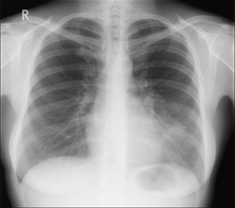

image

Figure 27.2 Female, 38 years. Chest pain. Silhouette sign...pneumonia in the lingular segments of the left upper lobe.